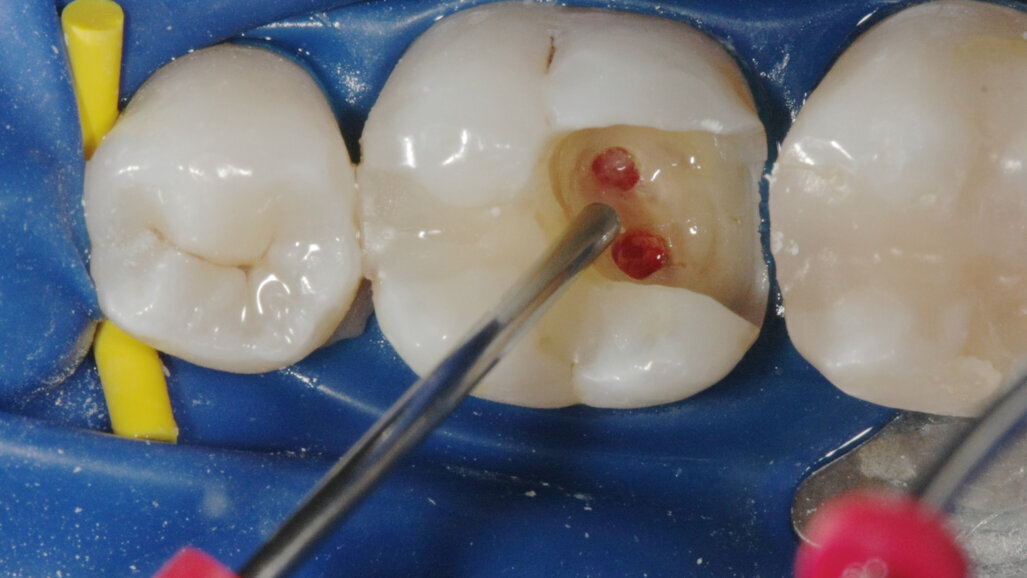

La terapia della polpa vitale è diventata più popolare negli ultimi anni. L’idrossido di calcio è stato il materiale più comune per l’incappucciamento della polpa, ma l’MTA ha mostrato risultati migliori in termini di biocompatibilità e risultati (Aguilar e Linsuwanont 2011). I casi con una grande esposizione della polpa cariosa possono essere trattati con successo con la pulpotomia parziale e l’MTA per l’incappucciamento, mantenendo i denti vitali (Figg. 1a-1e).

Incappucciamento della polpa